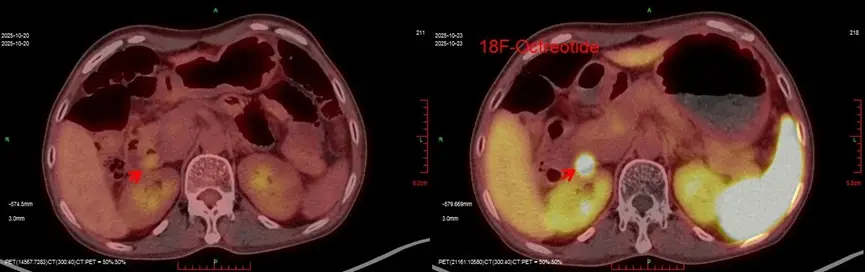

Sau khi loại trừ các bệnh lý nhiễm trùng và viêm tụy, các bác sĩ chuyên khoa đã xác định bệnh nhân có triệu chứng tiêu chảy tiết dịch. Đây là một dạng tiêu chảy hiếm gặp, thường liên quan đến u thần kinh nội tiết. Kết quả xét nghiệm máu cho thấy chỉ số chromogranin A tăng cao gấp 12 lần so với mức bình thường, điều này càng củng cố nghi ngờ lâm sàng về tình trạng của bệnh nhân.

Do khối u nằm tại vị trí giải phẫu phức tạp, sau khi hội chẩn và cân nhắc kỹ, các bác sĩ quyết định điều trị bằng nội soi cắt tách dưới niêm mạc (ESD), một phương pháp xâm lấn tối thiểu nhưng đòi hỏi kỹ thuật cao.

Ca can thiệp diễn ra thuận lợi, khối u được lấy ra, không ghi nhận biến chứng. Kết quả giải phẫu bệnh xác nhận đây là u thần kinh nội tiết độ G2, thuộc nhóm u tiết gastrin.